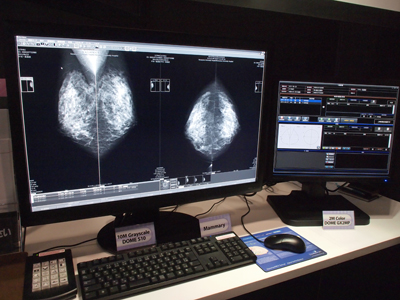

●自動キャリブレーションにより精度管理を効率化する液晶モニタ「DOME」シリーズ

エルクコーポレーションが販売を手がける液晶モニタの「DOME」シリーズは,出荷時のキャリブレーションデータを記憶して,常にDICOM Part14のGrayscale Standard Display Function(GSDF)に合った状態になるよう,自動キャリブレーション機能を搭載している。この機能により,長期間にわたり,精度の高い画像表示を安定して行うことが可能となっている。院内のフィルムレス化が進む中で,モニタ精度管理が課題となっているが,「DOME」製品はこの機能により,精度管理を効率化することを可能としている。

展示では,10メガピクセルグレーモニタ「DOME S10」のほか,4メガピクセルカラーモニタの「DOME 4Ec」などの「DOME E」シリーズが出品された。「DOME S10」はマンモグラフィ用モニタで,「DOME」製品のフラッグシップモデル。ベゼルレスにより画像の観察がしやすく,読影医の負担を軽減する。

![]() 「mammary」と組み合わせた10メガピクセルグレーモニタ 「DOME S10」 |

●CAD結果表示機能など搭載したマンモグラフィ専用画像診断ワークステーション「mammary」

「DOME S10」と組み合わされて展示されたのが,クライムメディカルシステムズ社のマンモグラフィ専用画像診断ワークステーション「mammary」である。ビューワとサーバの機能を兼ねたワークステーションで,CAD結果表示機能なども搭載される。レポートシステムである「Mammary Manager」は,チェック式の入力を追加採用するなど,効率的な読影を支援するインターフェイスを採用。キー画像の貼付やシェーマ図により,詳細なレポートを作成することができる。